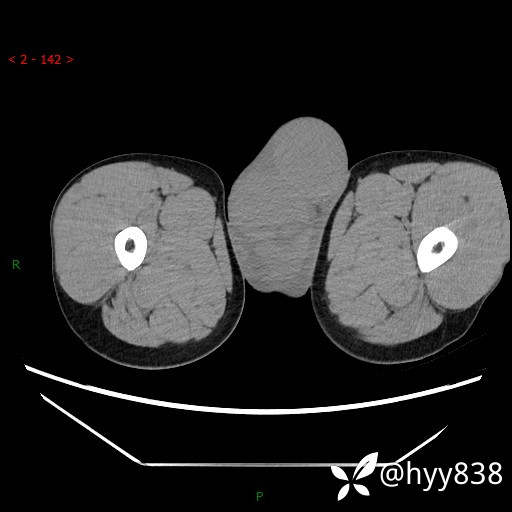

增强动脉期